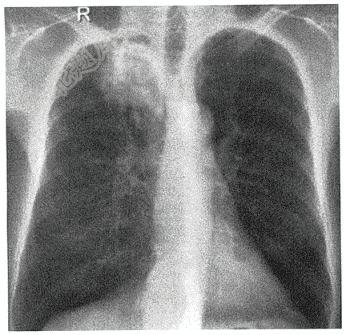

- 单项选择题男性,55岁,嗽咳、咳血1月( )

- 男性,55岁,嗽咳、咳血1月( )